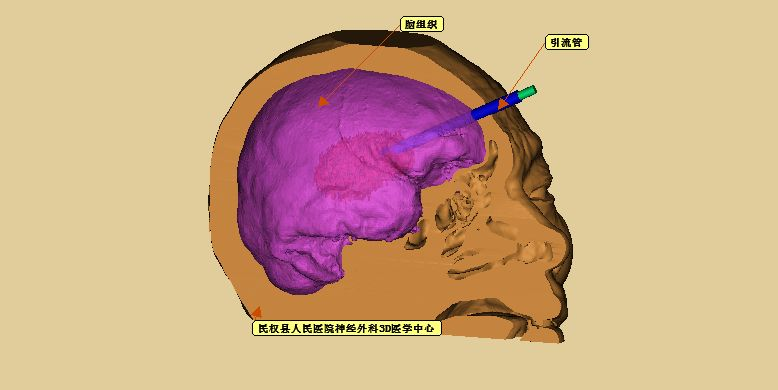

术前模拟设计,引流管位于血肿中心

术前模拟引流管经头部软组织、脑组织后穿刺进入血肿

重建脑组织并透视化显示引流管穿刺血肿

引流管与血肿、面部的导板关系